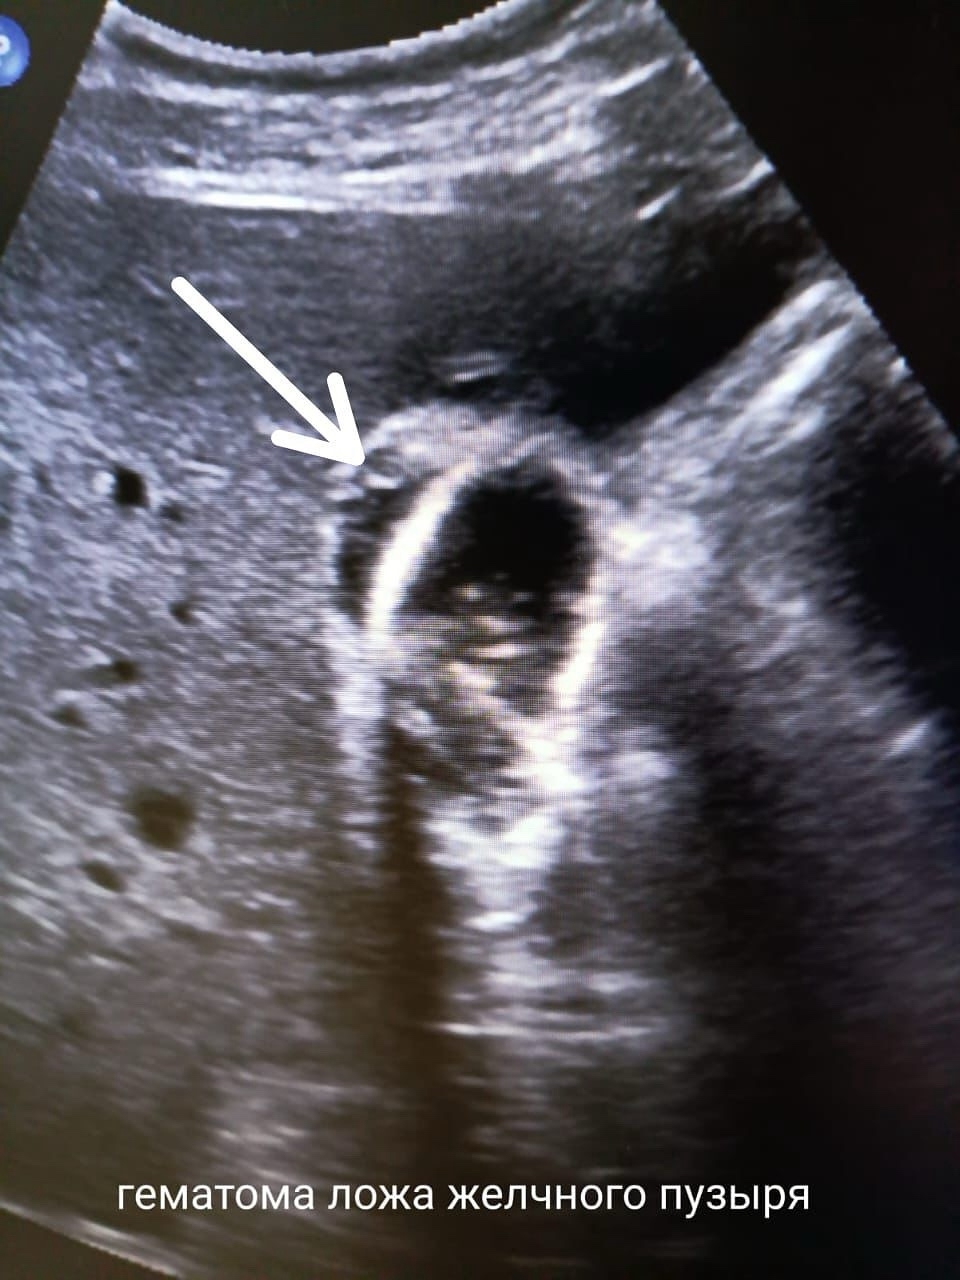

В этом случае в месте травмы сформировалась гематома. Была выбрана тактика консервативного ведения: динамическое УЗ-наблюдение, контроль анализов, гемостатические и антибактериальные препараты.

Гематома стабилизировалась и со временем полностью рассосалась, не потребовав хирургического вмешательства. Ключевой момент: желчный пузырь в результате был сохранен.